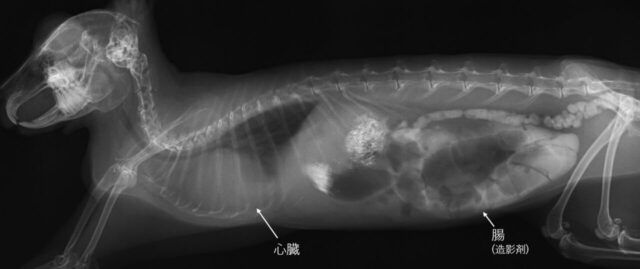

ずっとぎゅるぎゅる鳴り続けていたお腹は、うっ滞だけでなく鼓腸症という病気でガスが腸にパンパンに溜まっていることがわかりました。

あの不自然な歯軋りも鼓腸症によるお腹の痛みと心臓が肥大したことによる呼吸困難が原因とわかりました

レントゲンを撮ったところ、急性胃拡張で胃にガスがパンパンに溜まっているとのこと。非常に危険な状態なので、麻酔をかけてガスを抜く処置をするため、そのまま入院が決まりました。